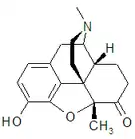

In the 19th century, two major scientific advances were made that had far-reaching effects. Around 1804, German pharmacist Friedrich Sertürner isolated morphine from opium. He described its crystallization, structure, and pharmacological properties in a well-received paper in 1817.[211][213][208][214] Morphine was the first alkaloid to be isolated from any medicinal plant, the beginning of modern scientific drug discovery.[211][215]

Several semi-synthetic opioids were developed in Germany in the 1910s. The first, oxymorphone, was synthesized from thebaine, an opioid alkaloid in opium poppies, in 1914.[228] Next, Martin Freund and Edmund Speyer developed oxycodone, also from thebaine, at the University of Frankfurt in 1916.[229] In 1920, hydrocodone was prepared by Carl Mannich and Helene Löwenheim, deriving it from codeine. In 1924, hydromorphone was synthesized by adding hydrogen to morphine. Etorphine was synthesized in 1960, from the oripavine in opium poppy straw. Buprenorphine was discovered in 1972.[228]

- Natural opiates: alkaloids contained in the resin of the opium poppy, primarily morphine, codeine, and thebaine, but not papaverine and noscapine which have a different mechanism of action

Opium alkaloids and derivatives

Opium alkaloids

Phenanthrenes naturally occurring in (opium):